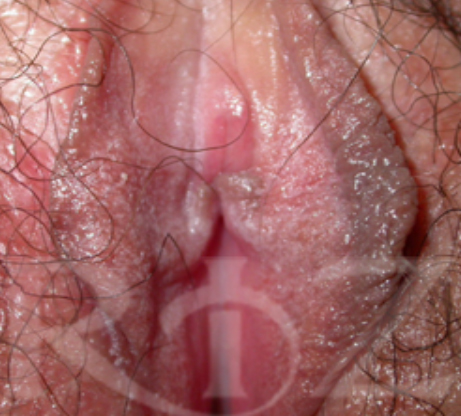

나이 : 31 / 출산경력 : 0 / 이름 : 최OO

- Before : 소음순 이상 Grade가 3~4도 정도 되며 생활에 불편을 느끼는 정도

- After : 손상된 부분이 디자인적으로 섬세하게 제거되었으며 핑크빛 소음순으로 재탄생 됨